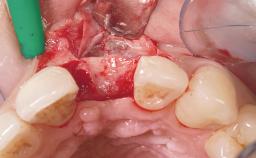

| Bone Augmentation | Horizontal|Simultaneous |

| Augmentation Materials | Xenogenous|Membrane |

| Soft Tissue Grafting | Simultaneous |